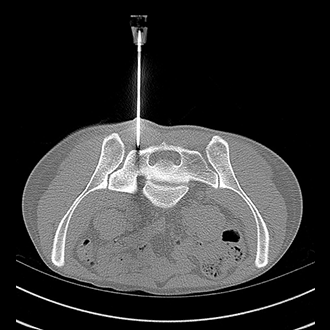

BIOPSY

Biopsy and Drainage

1. CT/USG guided biopsies.

2. CT/USG guided drainages.